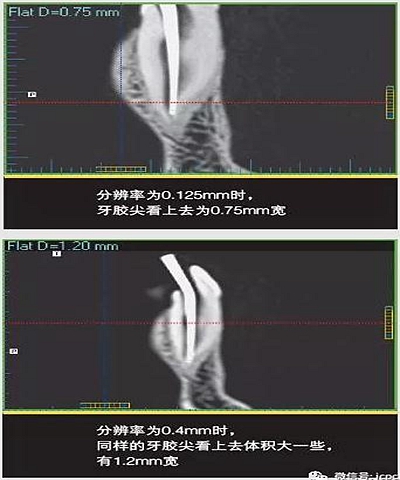

如果探測器中一個(gè)高對比度物體的體積小于體素尺寸,則該對象將會(huì)有效地填充入整個(gè)體素,使其看起來比實(shí)際物體大。牙膠周邊碎片的顯影就是其中一個(gè)很好的例子,如果牙膠周邊碎片的體積小于體素大小,則圖像上會(huì)看起來比實(shí)際的大。